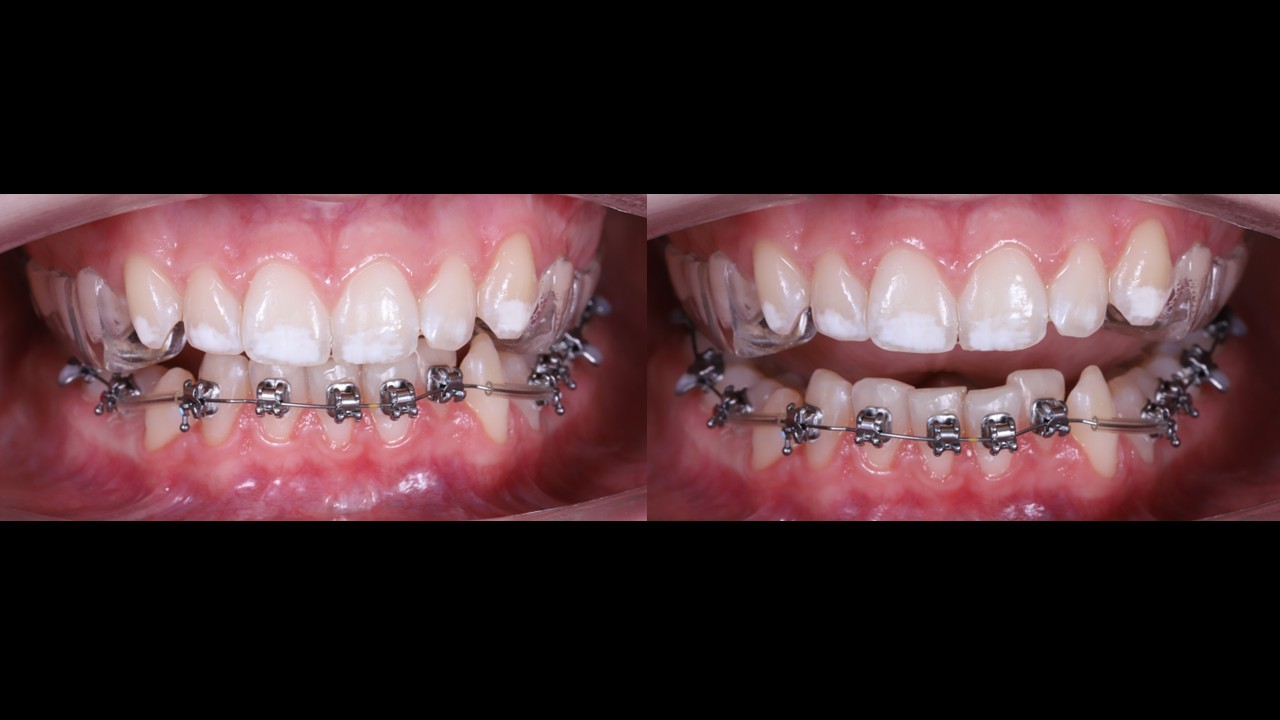

Як закрити відкритий прикус інтрузією бічних зубів

Все про закриття відкритого прикусу з контролем вертикального компоненту ISC-імплантами і плануванням по VTO. Без інтрузії навмання

→ Задаєш вертикаль ще на плануванні ортодонтичного лікування